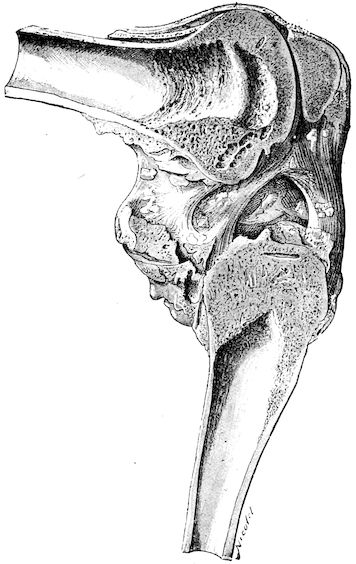

Lesions. The chief lesions are to be found in the bones. They consist in rarefaction of the compact tissue, increase in size of the medullary cavity and Haversian canals, and enlargement of the areolæ of the spongy tissue. The bone marrow loses its fatty constituents, appears red and gelatinous, and contains a greatly exaggerated number of blood-vessels. When heated, the bones do not yield oil as in healthy subjects, and when dry, they seem abnormally porous. In the osteoclastic phase, the bones become very friable and even the shafts assume 17a spongy appearance. They diminish in density. These changes correspond to the stages of eccentric rarefying ostitis and osteoporosis of German authors.

Fig. 8.—Transverse section through the middle region of the face in a pig suffering from osseous cachexia.

18In the final stages, the bones may be cut with a knife, and a time arrives when bony tissue seems completely to have disappeared; thus, as shown in Fig. 8 herewith, it was possible to cut the entire head of a pig into thin slices without the slightest difficulty. All parts of the head had been affected by the softening change.

From the chemical point of view, the diminution in mineral salts and in phosphate of calcium has long been recognised, but the degree of this change varies according to the phase. In human beings the proportions have been estimated as follows: Normal bone, 50 to 80 per cent. of phosphate of calcium; bone in persons suffering from osteomalacia, 5 to 20 per cent. of phosphate of calcium. The changes in the ossein have not been carefully studied. We only know that histologically the ossein becomes fibrillar, and that chemically it no longer retains its normal composition.